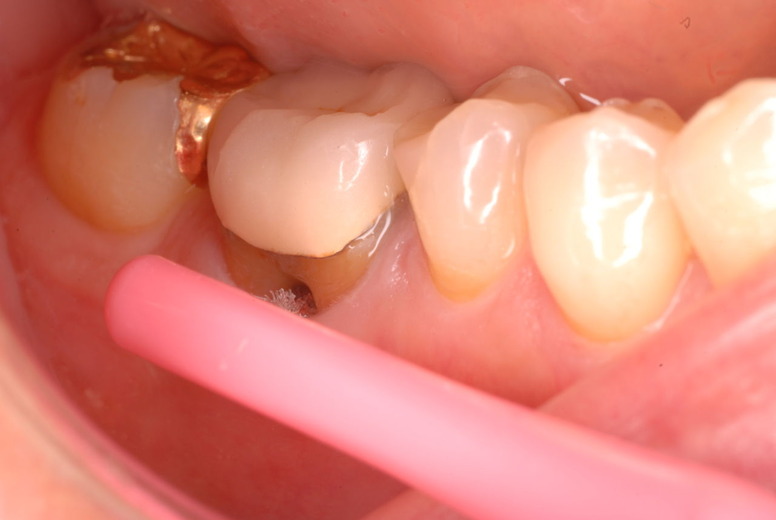

親知らずを取ることを嫌がる方が多いのですが、もし親知らずとその隣の14歳大臼歯の間に虫歯ができたり歯周病を罹患した場合、どれほど治療が大変で再発も起こりやすいか理解できない方がおおいのです。

写真左下の親知らずが痛くなり抜歯しました。その後歯茎を除去して虫歯を露出させる処置を二回ほどしています。

レントゲンでは小さいですが、こう言う虫歯が一番怖いのです。

治療の成功率は極めて悪くすぐ再発しやすいのです。